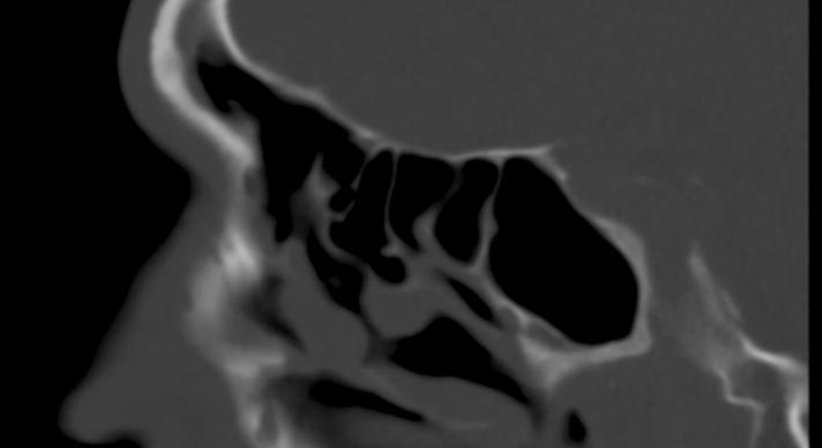

Hierbei handelt es sich um eine endoskopische Untersuchung mit einer starren, sehr dünnen Optik. In dieser Untersuchung können Polypen, Fremdgewebe wie Tumore oder chronische Entzündungen erkannt werden.

Sollten Sie an einer chronischen Sinusitis (Nebenhöhlenentzündung) leiden, kann ich Ihnen eine umfassende Beratung bezüglich aller therapeutischen Möglichkeiten anbieten.

Es gibt meistens zunächst die Möglichkeit einer medikamentösen Therapie. Sollte diese nicht den gewünschten Erfolg bringen, kann eine FESS (endoskopische Nasennebenhöhlen-Operation) durchgeführt werden. Ich erläutere Ihnen sehr gerne alle Wirkungen und Risiken dieser Operation.